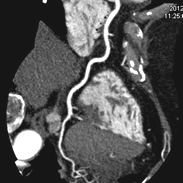

X線CT検査

X線装置を回転させることで、体内の断面像を画像として得ることができます。

造影剤という薬品を用いることで、血管や病変部を強調することもできます。

また、画像処理することにより、立体的な表示や血管部分のみを描出することもできます。

「診断部門」に320列CT装置と64列CT装置、救急外来に80列CT装置が稼働しています。

320列エリアディテクタCT装置のご紹介

この装置は、センサーが1回転する間に16cmの幅を撮影することができ、頭部や心臓などこれまでになく精確なスキャンを行うことができます。

- ・頭部領域

- 血管狭窄、動脈瘤、脳動脈奇形、脳腫瘍などの診断に威力を発揮します。また、造影剤を注入しながらスキャンを行うことで、4D画像を作成することができます。

- ・心臓領域

- 安定狭心症、急性冠症候群、経皮的冠動脈形成術・冠動脈パイパスの術後評価などに有用です。

64列CT装置に比べて息を止める時間が短くてすみ、患者様の負担が大幅に軽減されます。また、従来はよい画像を得ることが難しかった不整脈のある方についても、明瞭に描出する能力があります。 - ・体幹部領域

- 高速スキャンを用いますので、肩~骨盤部までが3秒程度ですみます。

撮影時に息を止める時間が短くてすむことにより、患者様の負担軽減と造影剤の注入量の軽減に大きく寄与します。 - ・検査被ばくの低減

- 被ばく低減システム「AIDR 3D」を用い、積極的に被ばくを低減したスキャンを行うことができます。

検査内容によって大きく異なりますが、被ばく線量を最大で従来の半分程度ですませることができます。